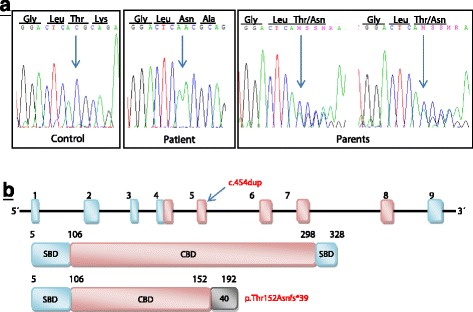

PCR amplification of genomic DNA followed by the sequencing of all nine exons and the intron-exon boundaries in the GRHPR gene (NM_012203.1) revealed several nucleotide variants. Homozygous synonymous variant c.579A > G (p.Ala193=, rs309458) and homozygous variant c.288-11C > T (rs2736664) were found in the exon 6 and intron 3, respectively. In the exon 5, we identified mutation c.454dup in homozygous form (Fig. 3a). This causal mutation has not been reported before [44] and results in a frameshift (p.Thr152Asnfs*39) after the insertion of a single A nucleotide. The frameshift generates a truncation of the GRHPR protein - from the original 328 amino acids to a 192-amino-acid-long polypeptide. In the truncated protein, the first 152 amino acids remain the same as in the wild-type protein, whereas the terminal 40 amino acids display an altered sequence. The frameshift causes the loss of two essential functional domains – the coenzyme-binding domain (CBD) and the formate/glycerate dehydrogenase substrate-binding domain (SBD). To get a full picture, we also analysed the DNA of both the patient’s parents. Sequence analysis of the GRHPR gene showed that both were heterozygous for the causal c.454dup mutation.

Fig. 3.

The structure of GRHPR gene and protein and sequences with mutation c.454dup. a Sequences show a control samples without mutation and a duplication of nucleotide A in homozygous (patient) and heterozygous state, which changes the followed amino acids from origin threonine to asparagine. The last two sequences are the parents of the patient. b Arrow shows the localization of this mutation in gene GRHPR (in exon 5) and diagram shows a predicted shorted protein. Boxes indicate exons and lines indicate introns. The coenzyme-binding domain (CBD) is indicated by a red box and two the formate/glycerate dehydrogenase substrate-binding domain (SBD) are indicated by blue boxes. The grey box indicates the length of additional amino acids that is appended as a result of the frame-shifting mutations

The assumption of PH2 was unequivocally confirmed by the molecular-genetic analysis of the GRHPR gene, which disclosed the presence of homozygous mutation c.454dup in the patient and the same mutation in heterozygous state in her parents. This homozygous form of mutation causes the frame shift after amino acid 152, which is followed by 40 novel amino acids and a premature stop codon at amino acid position 192. The generated protein has only 192 amino acids in comparison to the original 328 amino acids. The lacking of 136 amino acids is responsible for the loss of the important coenzyme-binding domain (CBD) of protein in position 107 to 298, and as well as the second domain of the two formate/glycerate dehydrogenase substrate-binding domain (SBD) located in the region 299–328 amino acids (Fig. 3b.) [24, 25].